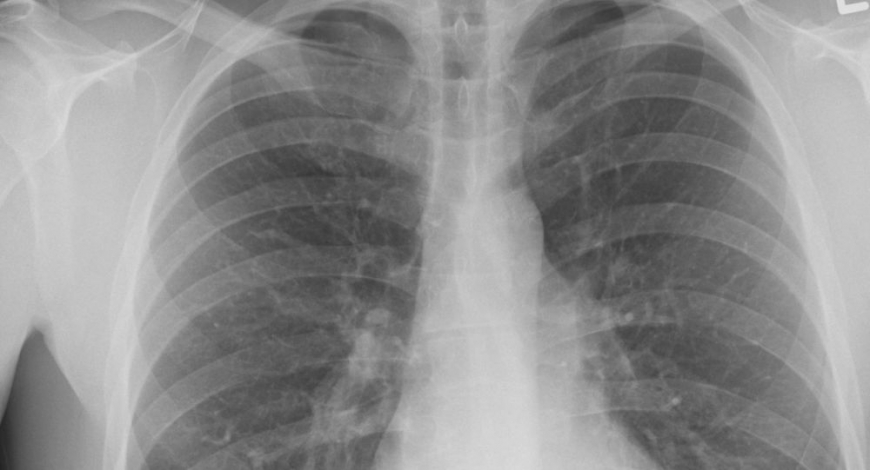

Количество новых случаев и рецидивов туберкулеза в 2018 году уменьшилось на 13,9% по сравнению с 2014 годом.…